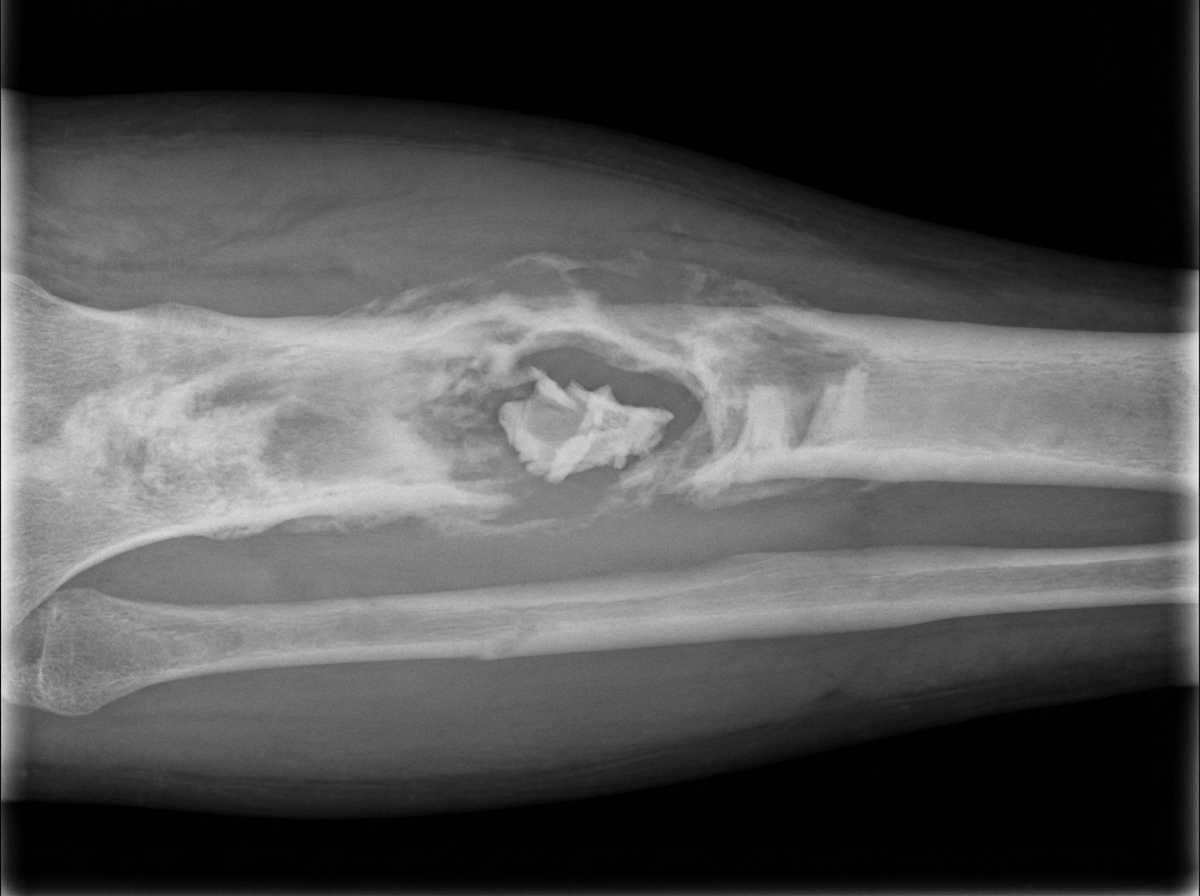

A patient has a history of similar symptoms at the same site two years ago, developing pain and swelling. X-ray shows the following features. What is the diagnosis?

Explanation: ***Chronic osteomyelitis*** - History of **recurrent pain and swelling** at the same site over 2 years is pathognomonic for chronic osteomyelitis with periodic **exacerbations**. - X-ray features include **sequestrum** (dead bone), **involucrum** (new bone formation), **cortical sclerosis**, and **periosteal reaction**. *Osteogenic sarcoma* - Typically presents as a **primary malignancy** in adolescents/young adults without history of recurrent episodes at the same site. - X-ray shows characteristic **sunburst appearance** and **Codman's triangle**, not the mixed sclerotic-lytic pattern of chronic osteomyelitis. *Ewing's sarcoma* - Usually affects children and adolescents as an **aggressive primary bone tumor** without chronic recurrent history. - X-ray demonstrates **onion-skin periosteal reaction** and **permeative bone destruction**, distinct from chronic osteomyelitis findings. *Multiple myeloma* - Presents in **older adults** (>60 years) with systemic symptoms like bone pain, anemia, and hypercalcemia. - X-ray shows characteristic **punched-out lytic lesions** without sclerosis or periosteal reaction, unlike chronic osteomyelitis.